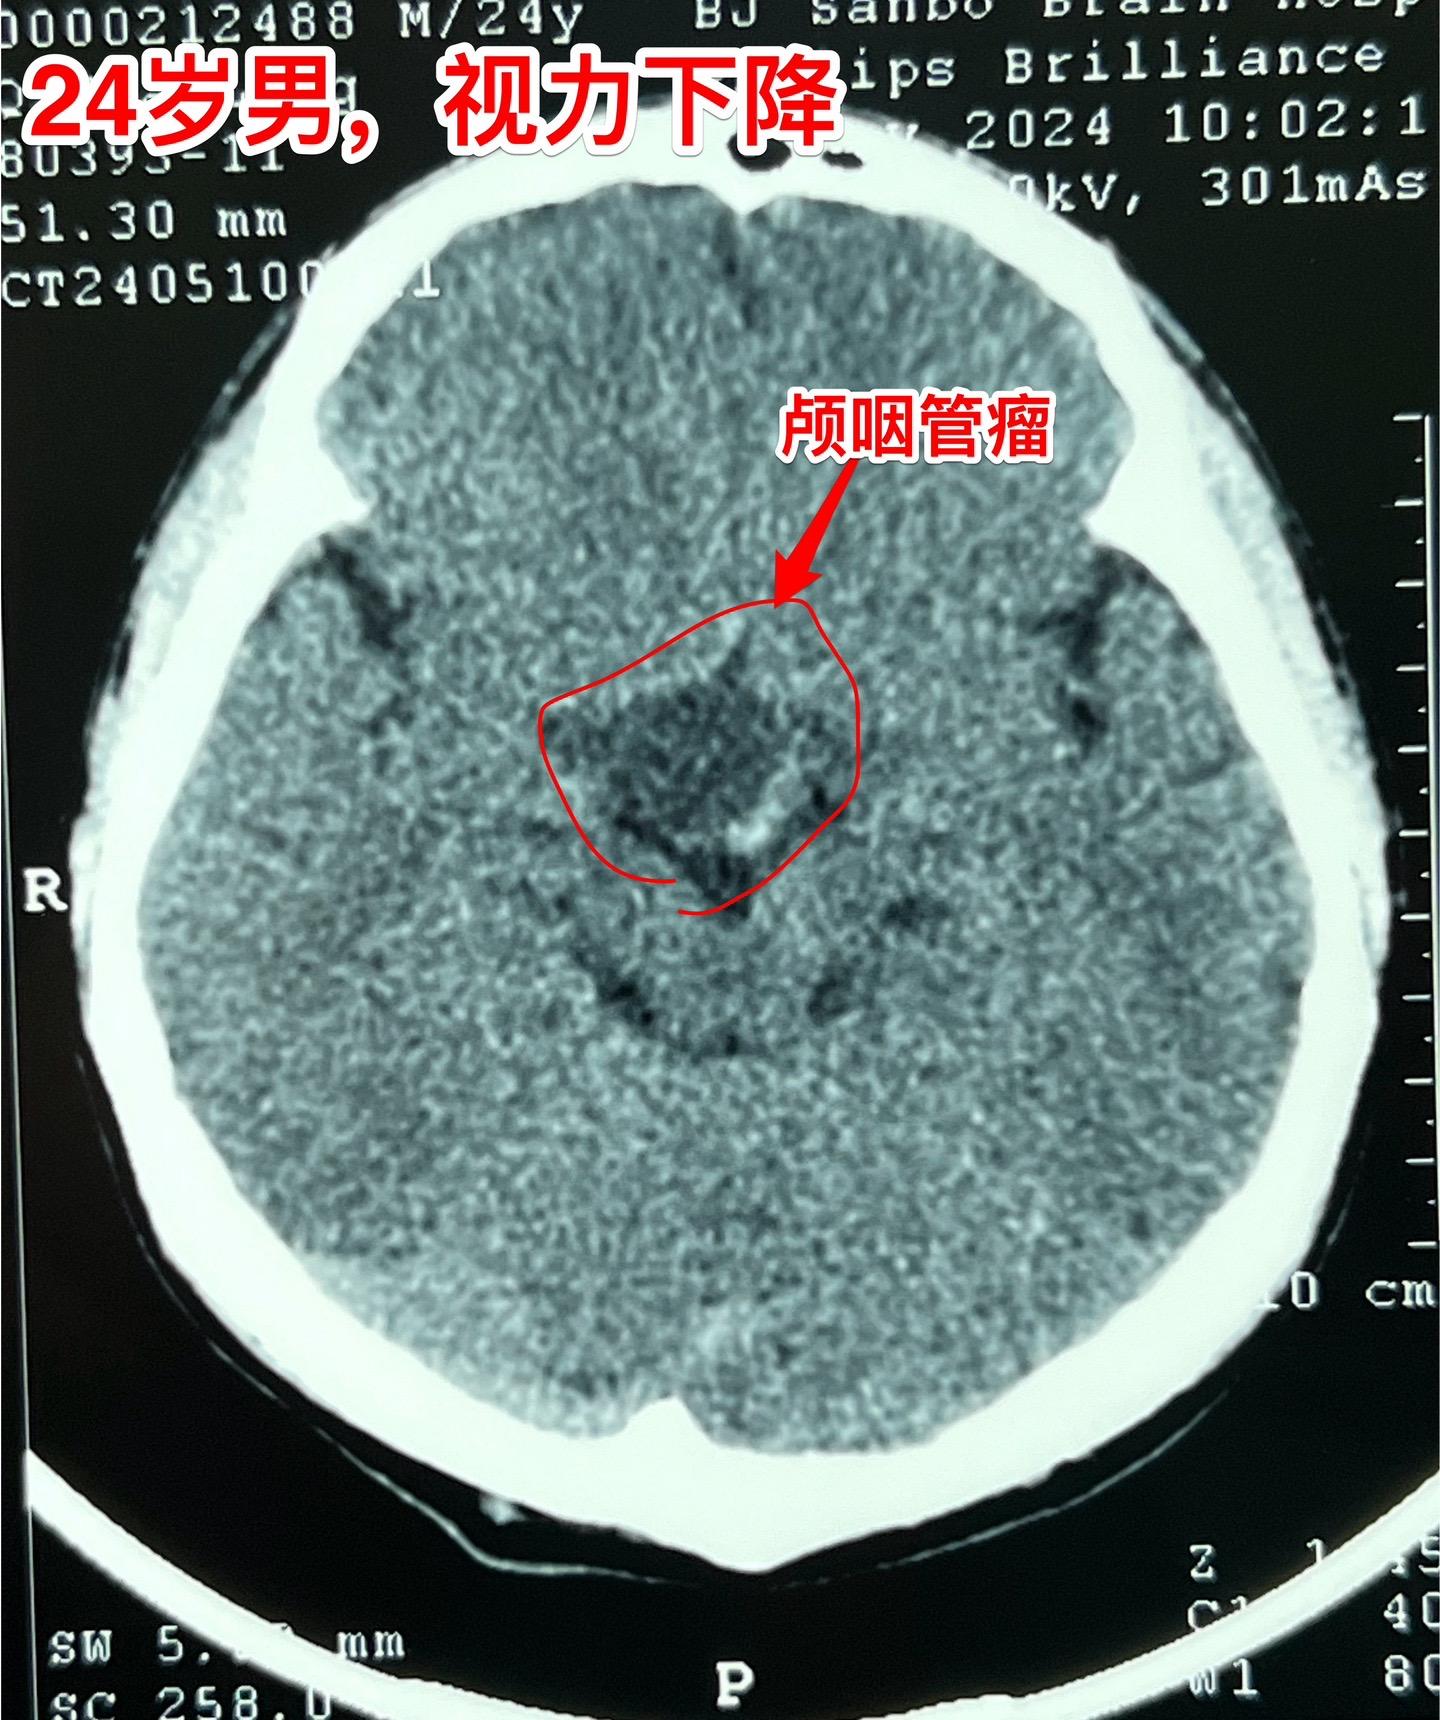

5月17日两例颅咽管瘤手术。第一例患者56岁,双眼视力都很差了,之前做过两次开颅手术,为乳头型颅咽管瘤复发。 第二例患者,24岁男性,因视力下降发现颅咽管瘤,也是乳头型颅咽管瘤。 两例患者手术入路不同,效果都满意,颅咽管瘤均得到完全切除。希望肿瘤不复发。